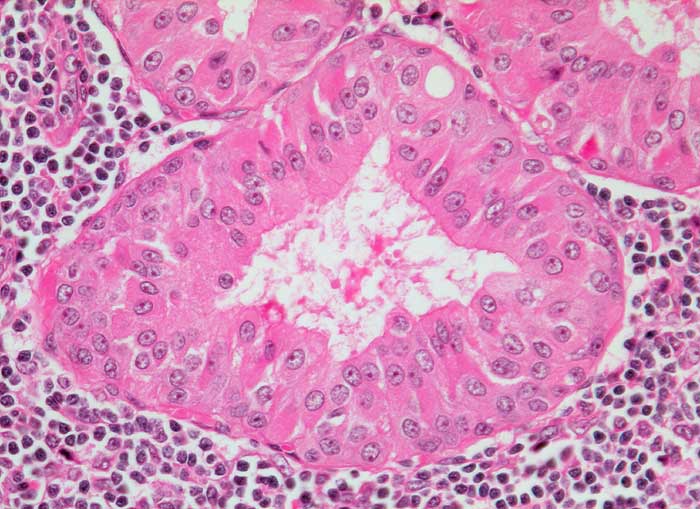

Der Warthin Tumor ist ein zystisch papillärer Tumor mit lymphoidem Stroma und einem zweischichtigen onkozytären Epithel. Schleim- oder Becherzellen und metaplastisches Plattenepithel können vorkommen. Die diagnostischen Zellen werden oftmals verdünnt durch den Zysteninhalt, was in einer falsch negativen Punktion resultieren kann. Im Idealfall enthält das Punktat Onkozyten und Lymphozyten auf granulär zystischem Hintergrund. Oftmals fehlen aber die Onkozyten. Differentialdiagnostisch muss man in solchen Fällen an eine lymphoepitheliale (oder branchiogene) Zyste denken. Onkozyten kommen bei einer Vielzahl anderer Parotisläsionen vor: onkozytäre Metaplasie oder Hyperplasie, Sjögren Syndrom, Onkozytom, Mucoepidermoidkarzinom, Adenokarzinom, adenoidzystisches Karzinom.